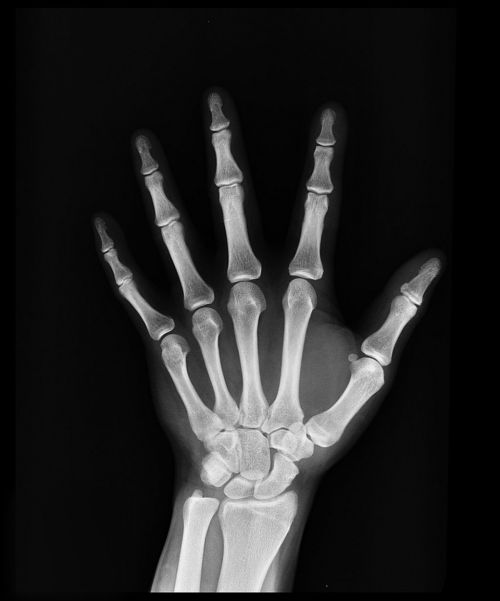

Лучевая диагностика не нарушает целостность тканей организма и никаких неприятных ощущений человек не испытывает. Суть процедуры в том, что рентгеновские лучи, проходя через тело поглощаются тканями, обладающими разной плотности.

Самая плотная ткань – костная, которая значительно ослабляет интенсивность лучей (поэтому на снимке они – светлые). Внутренние органы на снимках либо не отображаются, либо видны очень плохо и нечетко.

Такая диагностика используется преимущественно для выявления переломов и пневмонии (при исследовании грудной клетки).

Рентгенография – первый метод радиологического исследования, при котором на снимке запечатляются органы. Чтобы лучше просмотреть органы делают два снимка с разных сторон. На сегодняшний день проводится пленочный вариант рентгенографи, при котором человек облучается 0,5-0,8 мЗв, а также цифровой – дозой облучения в 0,1-0,2 мЗв.